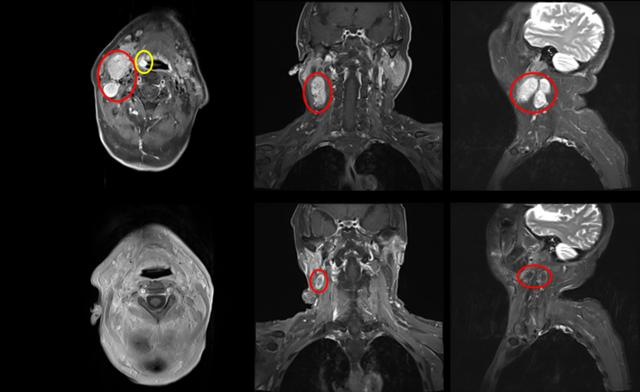

▲放疗前后对比

同时在采用精准的调强放疗方式下,张大爷总共放疗33次,辅以奈达铂每周化疗。放化疗期间副反应轻微,治疗结束后复查核磁共振提示扁桃体肿瘤消失,右侧颈部淋巴结缩小83%。